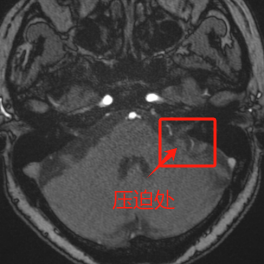

CT进一步检查……

经段友强主任详细问诊、检查后,赵女士被确诊为原发性面肌痉挛,病因是颅内血管压迫面神经。由于病程较长、症状较重,保守治疗已无法根治,需要通过微创手术从根源上解决问题。

显微镜下,面神经近侧头端被动脉压迫,分离血管后,用特殊垫片隔离,达到减压的目的,精准解除血管对面神经的压迫。